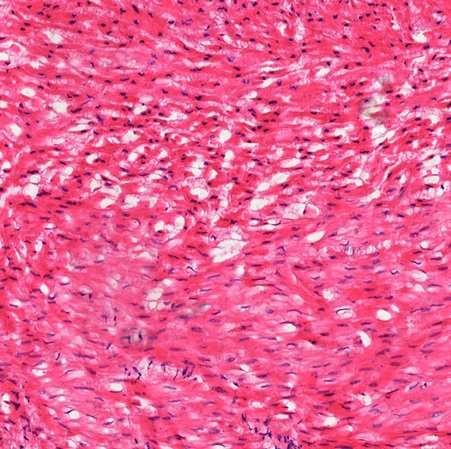

In the myocardium, cardiac muscle fibers form in bundles being sectioned longitudinally (L), transversely (T), and obliquely (O) respectively (Fig. 8-4). Different muscle bundles are separated by fibrous connective tissue (FC). The arrangement of complex, three-dimensional network allows the heart to contract in multiple directions simultaneously for maximum blood expulsion. The outermost epicardium (Fig. 8-5) is covered by a simple squamous mesothelium (SQM) deep to which is fibroelastic connective tissue (Fe). Nerves (N) and blood vessels (BV) can be found in the epicardium (Fig. 8-6).

The thick myocardium also has the arrangement of complex, three-dimensional network. Muscle fibers are seen to be sectioned longitudinally (L), transversely (T), and obliquely (O) respectively (Fig. 8-9). Similar to that of atrial wall, the outermost epicardium of the ventricle (Fig. 8-10) is covered by a simple squamous mesothelium (SQM). Between mesothelium and myocardium (My) is fibroelastic connective tissue.